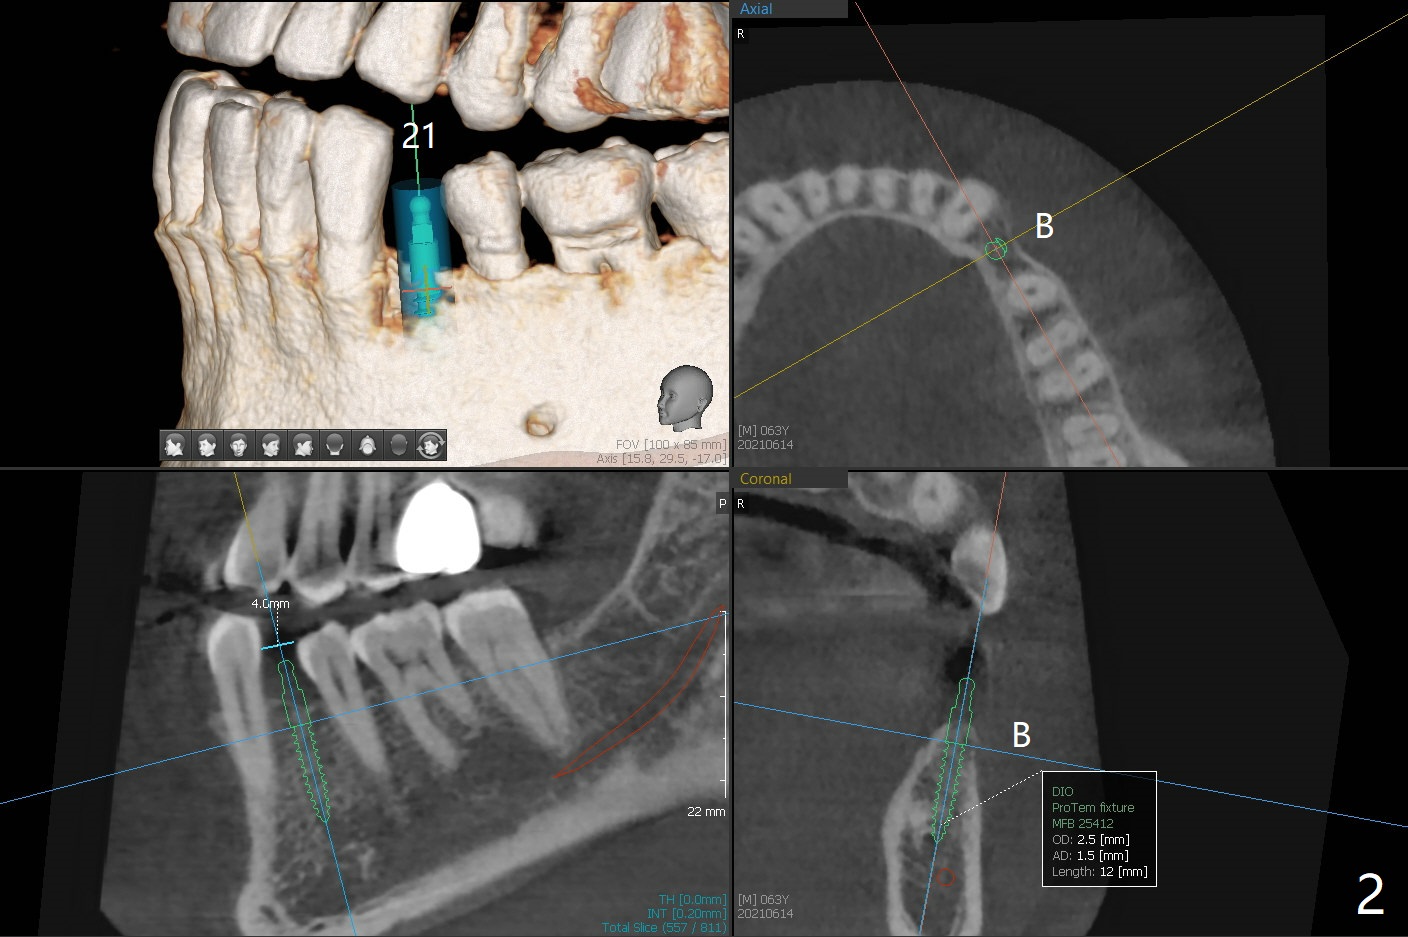

63岁男左上第一磨牙种植牙冠粘固后7年9月,终于同意在21号牙种植(图一),好像近远中间隙突然变小到不得不做牙齿矫正,其实下前牙拥挤(图二),可以关闭第一前磨牙间隙,或者推第二前磨牙和两个磨牙远中增加空间。缺牙间隙大约4毫米,能单纯植入2.5毫米一段式植体吗?而两旁牙齿邻面稍加修改来解决空间问题?